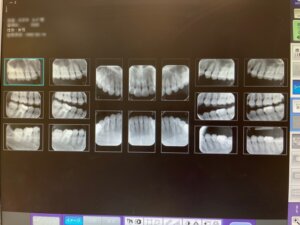

>>レントゲン検査(18枚法)

一本一本の歯を診査するためにレントゲンをお撮りします。

歯の周りの骨・かぶせ物・虫歯・根の病気をチェックします。

- 歯科用のレントゲンはサイズが小さく、レントゲンによるX線量はごくわずかなものであり心配はありません。〔日常生活で1年間あびている量の4~7/365〕

- 各種検査結果を資料にしてお渡しします。レントゲンのデータコピーなど希望される方がおられますが、データはjpgなどになり別途費用がかかります。現在日本の歯科レントゲンデータの規格は各メーカーにより統一されておらず、医院ごとに再撮影することがほとんどですので、あまりおすすめはしておりません。